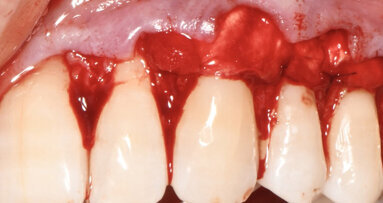

Fig. 6 - Visione occlusale del difetto trattato a 7 giorni di follow-up. Notare l’assenza di infiammazione e il tessuto guarito.

Fig. 7 - Visione frontale del difetto trattato a 30 giorni di follow-up. I parametri parodontali sono migliorati: PPD di 3 mm e CAL 4 mm. L’aspetto clinico dei tessuti è significativamente migliorato. L’edema della fase iniziale è rientrato e si nota una depressione al centro della papilla che evidenzia una fase avanzata della guarigione.

Fig. 8 - Visione occlusale del difetto trattato a 90 giorni di follow-up. La papilla è guarita con una retrazione del tessuto conseguente alla riduzione della profondità di tasca. La profondità di tasca si è ulteriormente ridotta: PPD di 2 mm e CAL 4 mm.